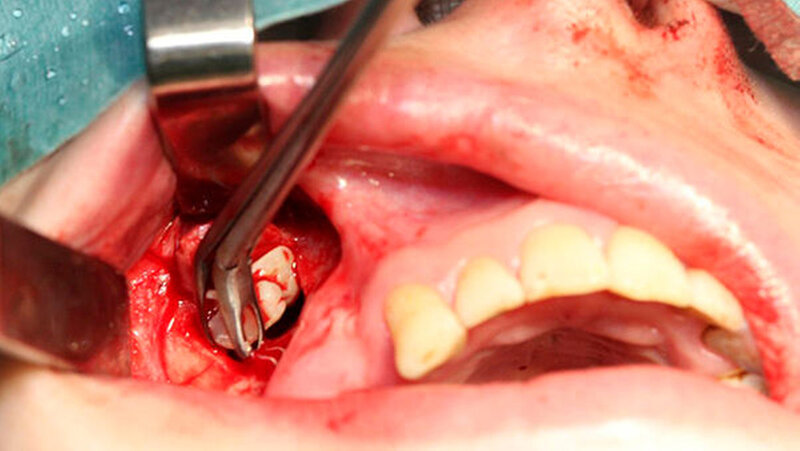

In Intubationsnarkose konnte der Fremdkörper aus dem rechten Sinus maxillaris über einen osteoplastischen offenen Zugang vestibulär regio 014 bis 015 geborgen werden (Abbildung 3). Die Mund-Antrum-Verbindung regio 026 wurde mittels eines Rehrmannlappens verschlossen. Gleichzeitig erfolgte die Entnahme von Proben aus beiden Kieferhöhlen. Die Abbildung 4 zeigt den kunststoffartigen Fremdkörper im Sinne von Füllungsmaterial. Die postoperative Röntgenkontrolle dokumentiert die Entfernung des Fremdkörpers (Abbildung 5) in toto.